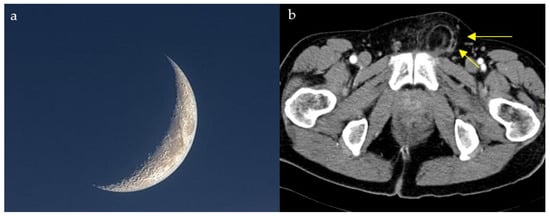

2.4. Loss of Half-Moon Overlap Sign

2.11. Crescent Sign

2.11.2. On Conventional Radiographs

2.12. Hyperdense Cresent Sign

2.13. Lateral Crescent Sign

2.14. Air Crescent Sign